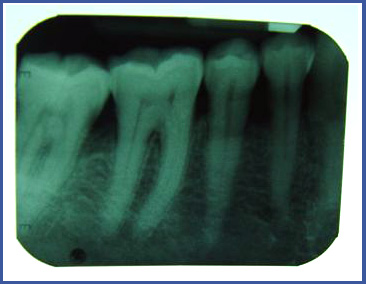

2. Прикорневой снимок (периапикальный)

Это отдельный снимок, который выполняется в стоматологической клинике и позволяет увидеть весь зуб – коронку и корень, а также твердые ткани (кость) вокруг зуба.

Снимки этого типа обычно выполняются во время лечения зубного корня, когда хотят проверить, существует ли воспаление вокруг корня или когда нужно выяснить высоту кости вокруг зуба.